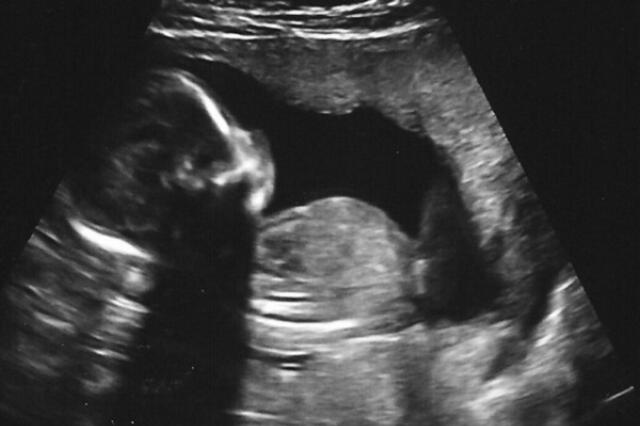

Image: Nogwater via Flickr, CC BY-SA 2.0 (cropped).